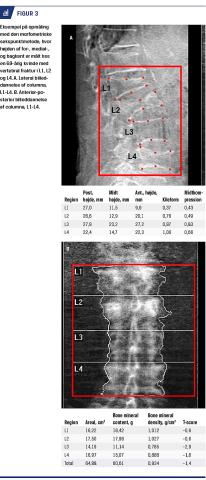

Man har i flere studier fundet relation mellem vertebrale frakturer og hoftenær fraktur [4, 6-9]. Det forekommer derfor ikke usandsynligt, at nogle hoftenære frakturer kunne være undgået, hvis de vertebrale frakturer var fundet, og patienten havde fået antiosteoporotisk behandling [23]. Studier har vist, at hvis man lader trænede undersøgere analysere VFA-billederne, opnås der øget reproducerbarhed, og antallet af falsk positive fund minimeres [24]. International Osteoporosis Foundation har udarbejdet kurser til træning af færdigheder i diagnostik af vertebrale frakturer ved brug af diverse billedmodaliteter, herunder VFA [25]. Ved anvendelse af VFA udsættes patienten for lavere stråledosis end ved andre radiologiske metoder, og kombinationen af VFA og dexa-skanning giver god mulighed for at få et overblik over patientens knogledensitet og frakturstatus. I den kliniske dagligdag er det netop disse to oplysninger, der bruges, når man skal beslutte, om der er indikation for behandling. Hvis der findes uerkendt vertebral fraktur, vil det ofte medføre, at man påbegynder behandling. I flere studier har man fundet god overensstemmelse mellem resultaterne af VFA og konventionel røntgenundersøgelse, og VFA er en billig og hurtig metode til diagnostik af vertebrale frakturer. Dog kan VFA kun anvendes til billeddiagnostik mellem Th4 og L4, og pga. billedkvaliteten er det ofte nødvendigt at ekskludere Th4 og Th5. Størstedelen af de vertebrale frakturer ses midttorakalt og på den torakolumbale overgang, netop der hvor VFA er diagnostisk velegnet. Optimal anvendelse af VFA kræver en passende klassificeringsmetode til diagnostik af frakturer, og i de gældende International Society of Clinical Densitometry (ISCD)-guidelines [26] anbefales Genants semikvantitative metode kombineret med den morfometriske metode (Figur 2 og Figur 3) [10]. Som flere af de omtalte studier belyser, kræver en optimal vurdering af VFA trænede undersøgere, og at der sammenlignes med konventionel røntgenundersøgelse ved tvivl om tilstedeværelse af vertebral fraktur eller anden patologi. I flere af de inkluderede studier belyses problematikken med overdiagnosticering af milde vertebrale frakturer, imidlertid vil tilstedeværelsen af en vertebral fraktur, uanset sværhedsgrad, medføre øget risiko for en ny vertebral fraktur [4, 5] og for en hoftenær fraktur [4, 6-8], og det er derfor vigtigt at medtage alle grader af vertebral fraktur i diagnostikken. I de officielle guidelines fra ISCD fokuseres der på ældre patienter med nedsat BMD-værdi [26]. Da der imidlertid er fundet vertebrale frakturer hos både mænd og kvinder med normal BMD samt hos personer under 60 år, synes disse anbefalinger at være for konservative. Hos patienter, der har risikofaktorer og lavenergifraktur, har man med VFA fundet vertebrale frakturer hos hver sjette

undersøgte [15]. Dette sammenholdt med, at flertallet af vertebrale frakturer initialt er asymptomatiske, gør, at VFA bør bruges mere [27]. I Danmark bruges case-finding strategy, og patienter, der er henvist for osteoporose, har alle de relevante faktorer, der øger risikoen for lav BMD-værdi og fraktur. Vi mener derfor, at patienter, der er henvist til undersøgelse for osteoporose, ud over BMD-måling bør få foretaget en vurdering af eventuelle vertebrale frakturer. Dette kan gøres med VFA-måling samtidig med dexa-skanning eller med konventionel røntgenundersøgelse. Når VFA er udført, bør det ved svarafgivelse til den henvisende læge også fremgå, om der er vertebrale frakturer. Ved tvivl om tilstedeværelse af en vertebral fraktur eller anden patologi bør der opfordres til yderligere radiologisk undersøgelse. Ved dexa-undersøgelser bør det endvidere vurderes, om patienten kan have falsk forhøjede BMD-værdier. Disse forhøjede værdier kan bl.a. skyldes aortaforkalkning, degenerative tilstande i columna og vertebral fraktur, og også her kan VFA gavne patienten. På Figur 3 ses en 69-årig kvinde med vertebral fraktur i L1, L2 og L4. På grund af dette er BMD-værdierne for disse vertebrae alle placeret inden for normalområdet, og patienten kunne risikere at blive klassificeret som værende uden osteoporose, trods svær sygdom.